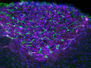

FAK Checker

The most common brain tumour glioblastoma, despite attempts to treat, is usually rapidly lethal (average survival 1–1.5 years) due to highly active glioblastoma stem cells with flexible metabolic needs. Here, in a mouse model, an enzyme called FAK is found to be key in controlling glioblastoma stem cell energy usage and presents a possible target for slowing down deadly cell growth